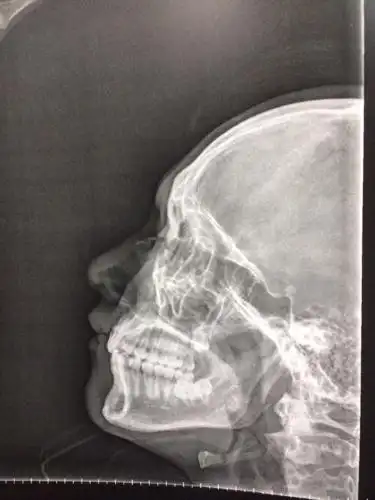

本人最近和别人发生打架事件,致使本人鼻骨骨折.